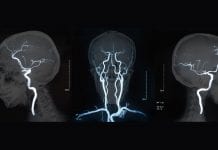

Neuromelanin-sensitive MRI discovered as potential psychosis biomarker

NIH-funded study found that a type of magnetic resonance imaging, called neuromelanin-sensitive MRI (NM-MRI) is a potential biomarker for psychosis.

Neuromelanin-sensitive MRI signal was found...